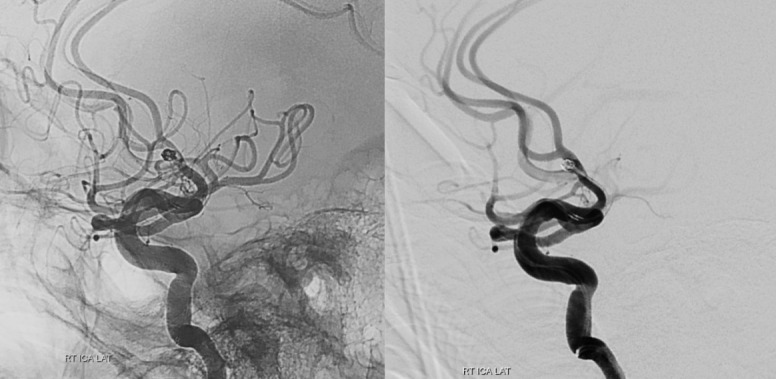

Abstract Image